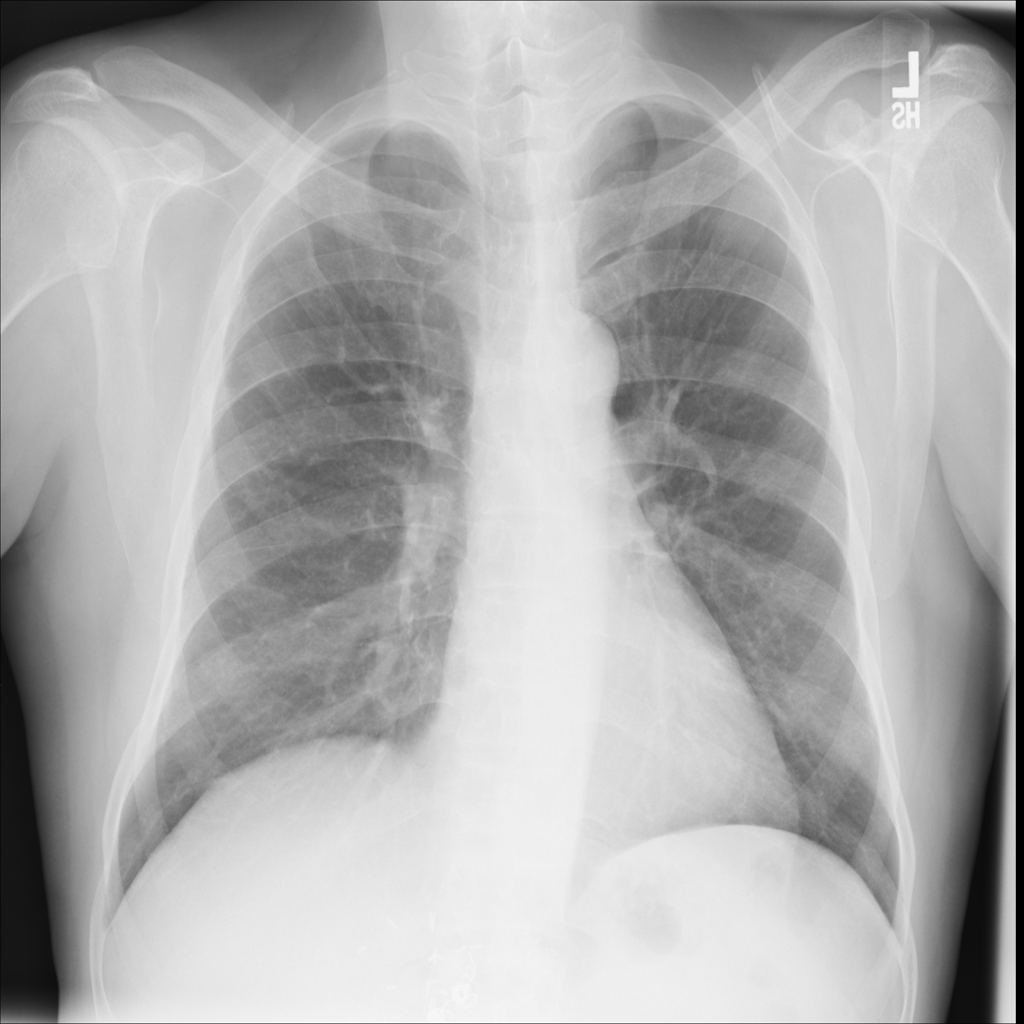

PAT-DB80 · IMG-001Atelectasis

PAT-DB80 · IMG-001

PA